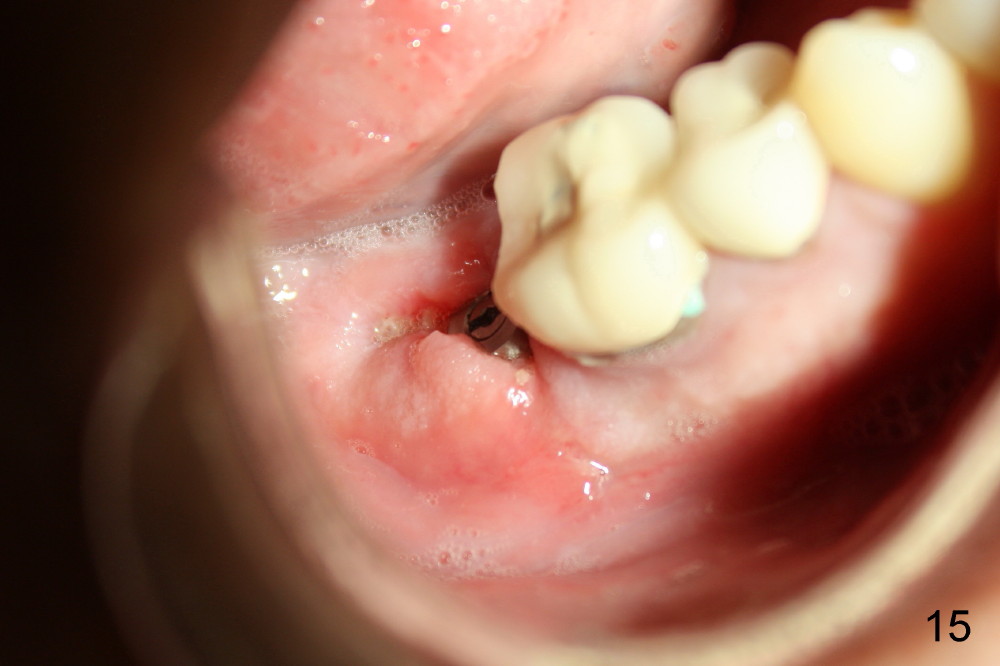

The flap is sutured to cover the gingiva-level implant for hemostasis. Fig.14 shows the wound 7 days postop. The implant is exposed 3 weeks postop (Fig.15).